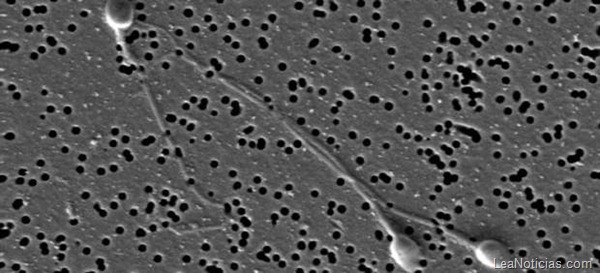

La infertilidad masculina requiere un análisis exhaustivo del esperma para conocer qué origina el problema del paciente y orientarlo hacia el tratamiento más indicado. Ahora, un equipo de la Universidad Autónoma de Barcelona (UAB) ha patentado un método para precisar el grado de infertilidad del hombre.

El procedimiento permite precisar de manera sencilla, económica y fiable la infertilidad de un individuo mediante el estudio del estrés oxidativo de los espermatozoides, un parámetro poco estudiado hasta ahora. Actualmente, el 15% de las parejas en edad de procrear son infértiles y en el 50% de los casos el factor masculino está presente.

El 15% de las parejas son infértiles; en el 50% de casos por el hombre. Los principales parámetros que se estudian actualmente son la concentración, la movilidad y la morfología espermática, aunque recientemente se ha comenzado a considerar un nuevo parámetro para detectar la infertilidad, la fragmentación del ADN espermático.

El estrés oxidativo de los espermatozoides es el principal responsable de la fragmentación del ADN, por ello la determinación de este parámetro puede justificar la presencia de esta fragmentación y descartar otros factores. Todo ello servirá para que el médico pueda determinar la necesidad o no de recetar tratamientos con antioxidantes a quien realmente lo necesite.